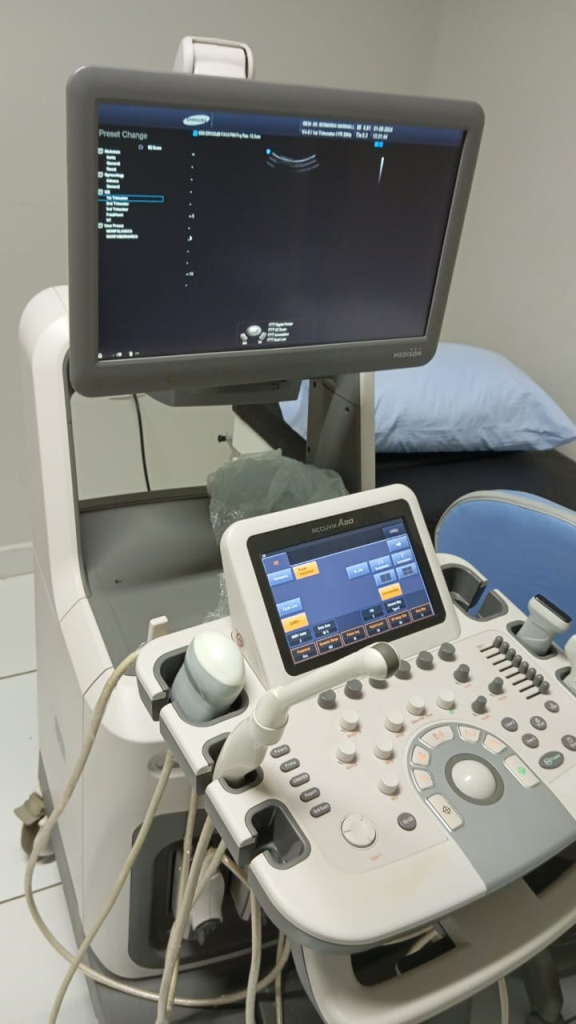

O Accuvix A30 é um upgrade da Samsung ao já poderoso Accuvix XG, adicionando imagiologia 4D de elevada resolução. Estabelece novos padrões operacionais com funcionalidades como EZ Exam e ElastoScan.

Transdutores: Linear, Convexo, Endocavitário e 4D

Transdutores: Linear, Convexo, Endocavitário e 4D